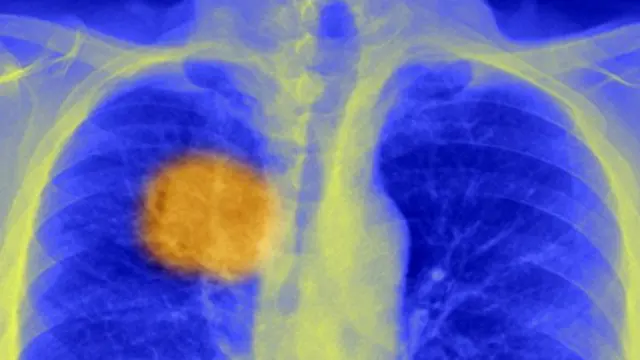

பட மூலாதாரம், SPL

புற்றுநோய் உள்ள செல்களுக்கு உள்ளே, இயல்பாகவே இருக்கும் பலவீனம் ஒன்றை தாம் கண்டறிந்துள்ளதாக யுனிவர்சிட்டி காலேஜ் ஆஃப் லண்டனைச் (யு.சி.எல்) சேர்ந்த விஞ்ஞானிகள் தெரிவித்துள்ளனர்.

உடலில் உள்ள சிறப்பான நோய்த்தடுப்பு செல்களான T- செல்கள், புற்றுநோய் கட்டிகளை கண்டறிந்து அழிக்க வழி ஏற்படுத்துவதாக இந்த கண்டுபிடிப்பு உள்ளது.